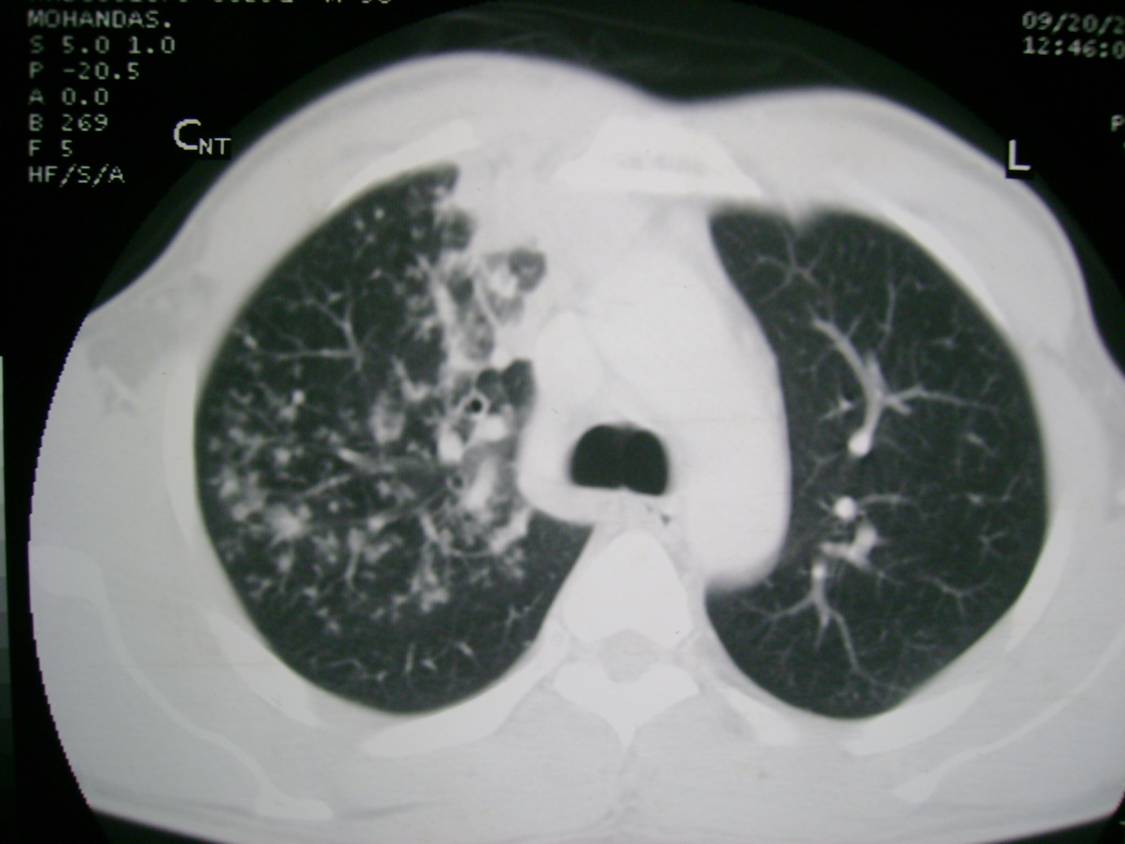

Tree in Bud